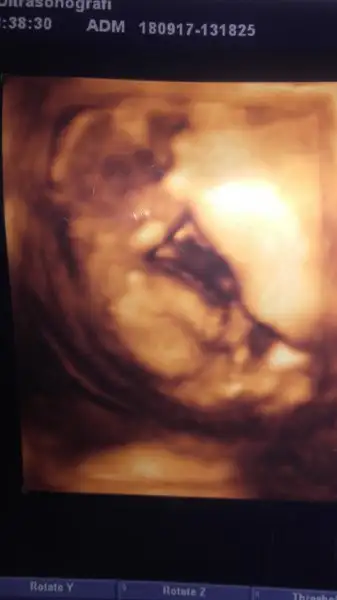

kizlar merhaba kontrolden geldim simdi yine cinsiyetini ogrenmeden yarim saat ayrintili baktik ama doktor bisey soylemedi bir ara sarkan bisey gorduk gibi olduk oynatti bebegi kayboldu kordondu buyuk ihtimalle. bana kiz gibi geldi bakallim 10 gun sonra yine gidicem ozaman net ogrenicez insallah

Eklentiler

• 20170918_141716.webp

6,9 KB · Görüntüleme: 90